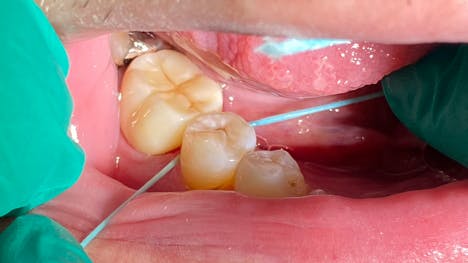

My fifth—and probably most important—tip is to invest in a computer-aided anesthetic device. Specifically, I use the Calaject from Directa Dental, which I’ve found to be the most versatile and cost-effective unit available. This device dispenses local anesthetic at a controlled flow rate, using the back pressure from the anesthetic to allow for precise and pain-free injection. Most of us know that the pain from an injection comes from adding liquid volume into a space that cannot expand to accommodate it. Calaject’s design follows scientific recommendations for the speed and pressure of anesthesia administration, ensuring a pain-free and comfortable experience for patients.

The Calaject system is designed to replace traditional injection techniques. It consists of three components: the main module with a long-lasting rechargeable battery and easy-to-clean control panel, a small foot pedal that connects to the main module, and a pen-shaped handpiece that eases anxiety by replacing the traditional dental syringe. The handpiece features a clear, autoclavable barrel that holds the anesthetic cartridge and needle, and it also has an auto-aspiration feature that prevents anesthetic from leaking where it’s not needed. The system offers three separate modes for intraligamental/palatal injections, infiltrations, and regional blocks, along with a prominently featured pressure gauge, which is critical for live feedback during PDL/palatal injections.